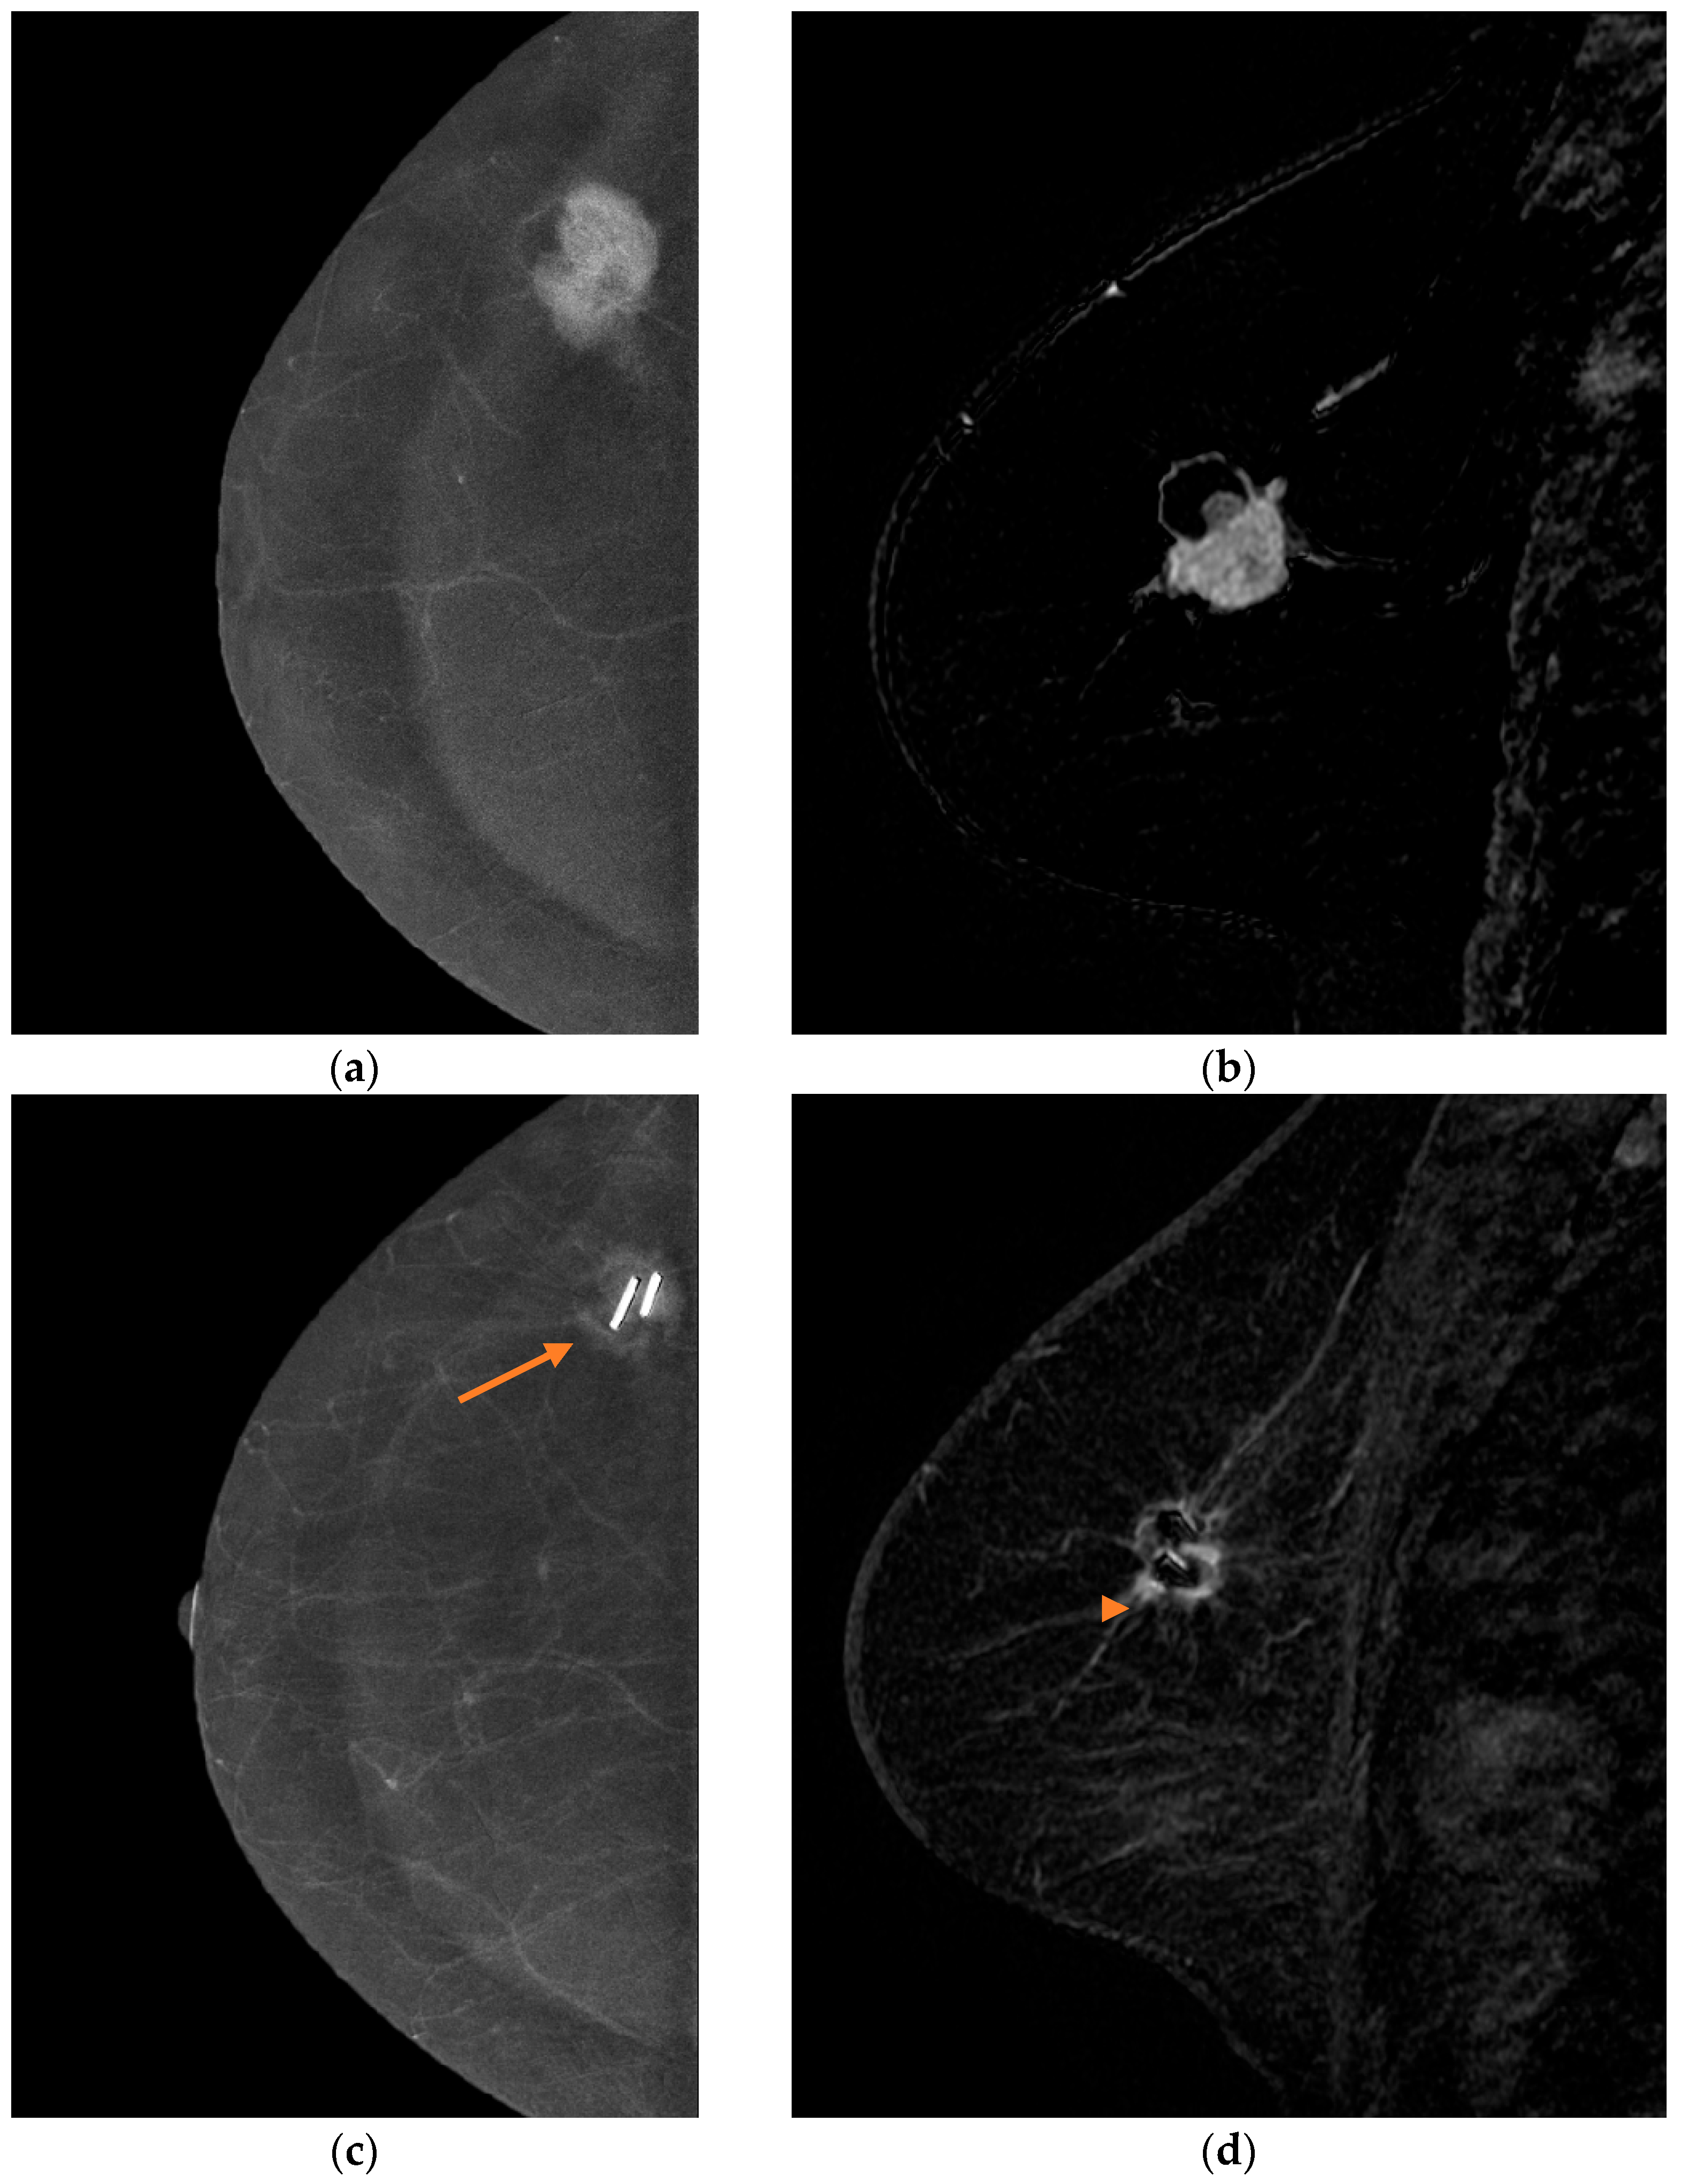

2.4.1. Contrast-Enhanced Mammography (CEM)

2.4.2. Breast Magnetic Resonance Imaging (MRI)